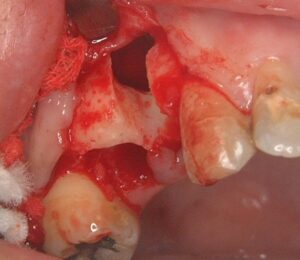

嚢胞を除去したところです。かなり穴があいています。